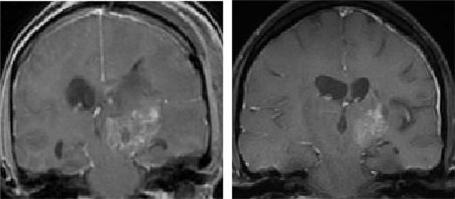

Malignant gliomas are invasive tumors with the potential to progress through current available therapies. These tumors are characterized by a number of abnormalities in molecular signaling that play roles in tumorigenesis, spread, and survival. These pathways are being actively investigated in both the pre-clinical and clinical settings as potential targets in the treatment of malignant gliomas. We will review many of the therapies that target the cancer cell, including the epidermal growth factor receptor, mammalian target of rapamycin, histone deacetylase, and farnesyl transferase. In addition, we will discuss strategies that target the extracellular matrix in which these cells reside as well as angiogenesis, a process emerging as central to tumor development and growth. Finally, we will briefly touch on the role of neural stem cells as both potential targets as well as delivery vectors for other therapies. Interdependence between these varied pathways, both in maintaining health and in causing disease, is clear. Thus, attempts to easily classify some targeted therapies are problematic.

恶性胶质瘤是侵袭性肿瘤,即便采用现有的治疗方法仍有可能进展。这些肿瘤的特征是在分子信号传导方面存在许多异常,这些异常在肿瘤发生、扩散和存活中发挥作用。在临床前和临床环境中,这些信号通路都在作为恶性胶质瘤治疗的潜在靶点被积极研究。我们将综述许多针对癌细胞的疗法,包括表皮生长因子受体、雷帕霉素哺乳动物靶点、组蛋白去乙酰化酶和法尼基转移酶。此外,我们将讨论针对这些细胞所处的细胞外基质以及血管生成的策略,血管生成是肿瘤发展和生长的核心过程。最后,我们将简要提及神经干细胞作为潜在靶点以及其他疗法的递送载体的作用。这些不同信号通路在维持健康和引发疾病方面的相互依存关系是显而易见的。因此,试图简单地对某些靶向疗法进行分类是有问题的。